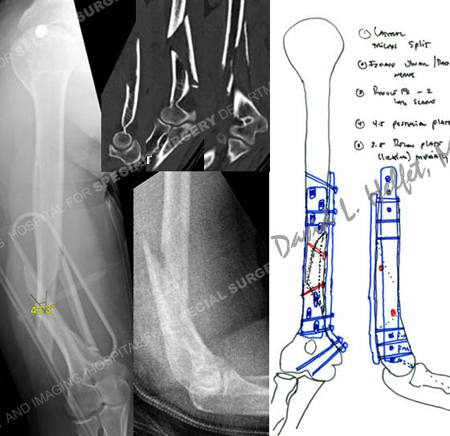

Anteroposterior and lateral radiographs reveal a displaced humeral fracture with a medial butterfly fragment and CT images further delineate the fracture pattern (top images). Plate fixation in a 90/90 fashion was planned.